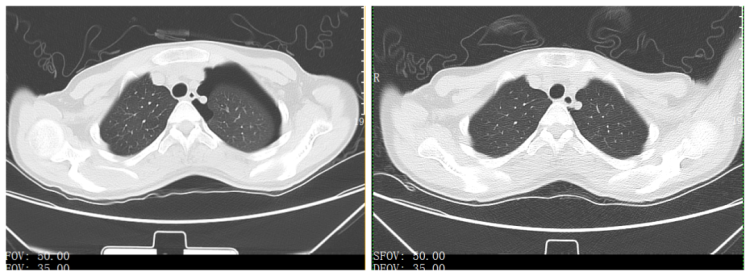

治疗前后CT对比

小郑身高168厘米、体重45公斤,是典型的“抽条期”少女。那天,小郑正准备唱一个完美的高音C,意外突然发生。老师和队员发现后,紧急将她送往宁波市中医院。诊断结果出乎所有人的意料:她确诊为“左侧自发性气胸”,肺压缩达40%。所幸抢救及时,经过胸腔闭式引流和中药调理,小郑如今已康复出院。